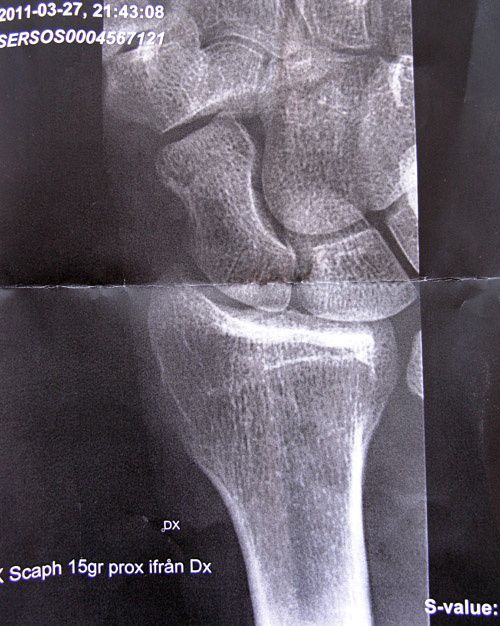

Skillnad på behandling av frakturer i båtbenet dels beroende på var brottet sitter, dels beroende på hur mycket benbitarna har åkt isär. Mathias fraktur på bilden ovan är en "snäll" typ ur båda de synvinklarna, därför får du ingen skruv.

Båtbenet har en mkt viktig funktion i handleden, om inte läkningen får gå rätt till är risken stor att man förr eller senare får artros i lederna kring båtbenet, viktigast förstås handleden.

Båtbenet blodförsörjs av en artär från distala änden, alltså änden som är längst bort från kroppen. Därför kan en fraktur genom "midjan" på båtbenet, eller ännu närmare handleden, leda till att proximala delen, dvs delen närmast handleden, dör och skrumpnar, och man får naturligtvis en dåligt fungerande handled som följd. Därför skruvas många midjefrakturer och i stort sett alla frakturer som är ännu närmare handleden. Frakturer längst bort i båtbenet är inte alls lika känsliga och kan gipsbehandlas.

Och nej, där är ingen distal radiusfraktur på bilden.

Tack för info! Allmänläkaren som tog emot mig på SöS var inte säker på fraktur. På min papperskopia ser man brottet tydligt om man tittar noga så jag är imponerad att du ser det på min dåliga/lilla bild här.